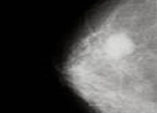

- МАММОГРАФИЯ

До последнего времени основным методом ранней диагностики опухолей молочной железы считалась маммография, позволяющая сделать

рентгеновский снимок железы. Кроме рентгеновского облучения пациента у этого метода есть еще один недостаток, а именно: достоверность

диагноза во многом зависит от квалификации специалиста расшифровывающего снимок.